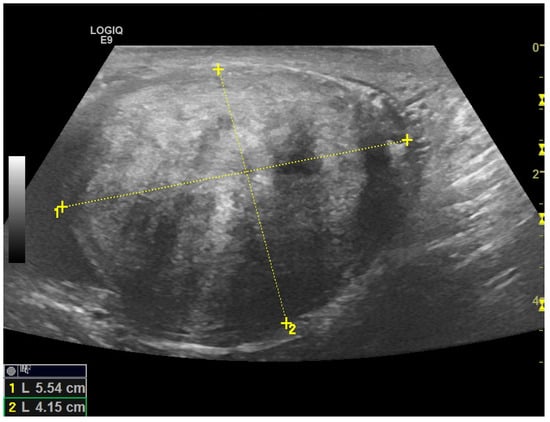

Scrotal US examination was performed using a Logic E9 unit (GE Healthcare) with linear probes (ML 6–15-D—4.5–15 Mhz and 9L-D 3.0–8 Mhz). B-Mode US revealed a rounded, hyperechoic, and coarsely heterogeneous solid mass within the lower part of the left hemiscrotum measuring 4.8 × 4.1 cm in size. The left testis was lifted by the mass, from which it was poorly dissociable at the lower pole; however, it was preserved in size and echostructure (Figure 2 and Video S1). The contralateral testis and epididymis appeared to be normal. Mild fluid was also noted in the scrotal sac, which was consistent with a hydrocele.

Figure 2. High-frequency 15 MHz B-Mode US image shows a large, solid paratesticular mass at the lower pole of left testis. The mass has an echogenic, coarsely heterogeneous echotexture.